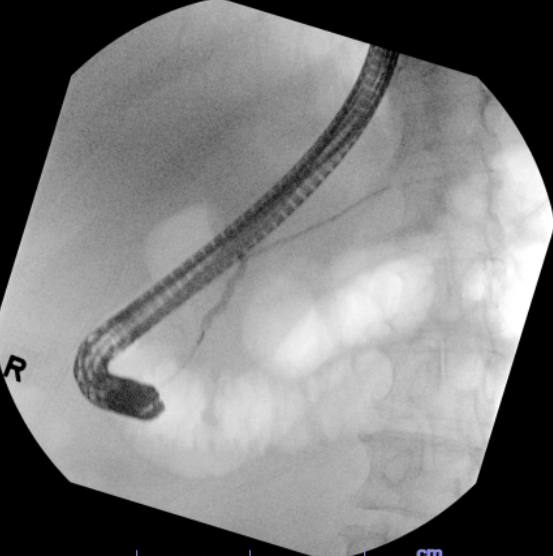

A double whammy case of a PD leak post splenectomy for splenic laceration in the setting of a pancreatic head mass prohibiting retrograde PD wire passage. EUS guided pancreaticogastrostomy with placement of a double pigtail stent was performed with resolution of leak. #GITwitter